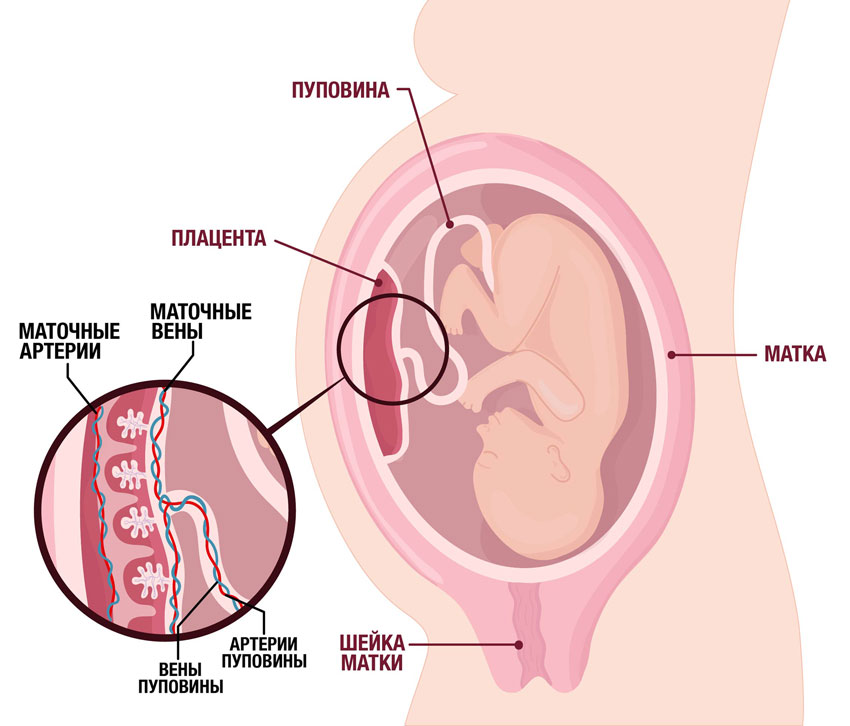

Физиология беременности: строение органов

Раздел: Моменты озарения